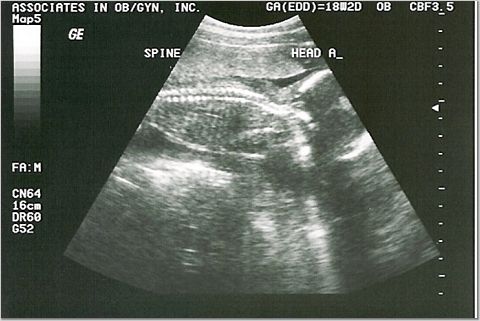

18 weeks - 7 & 8 ounces

We were supposed to find out the sexes, but they were too active for the tech to see!